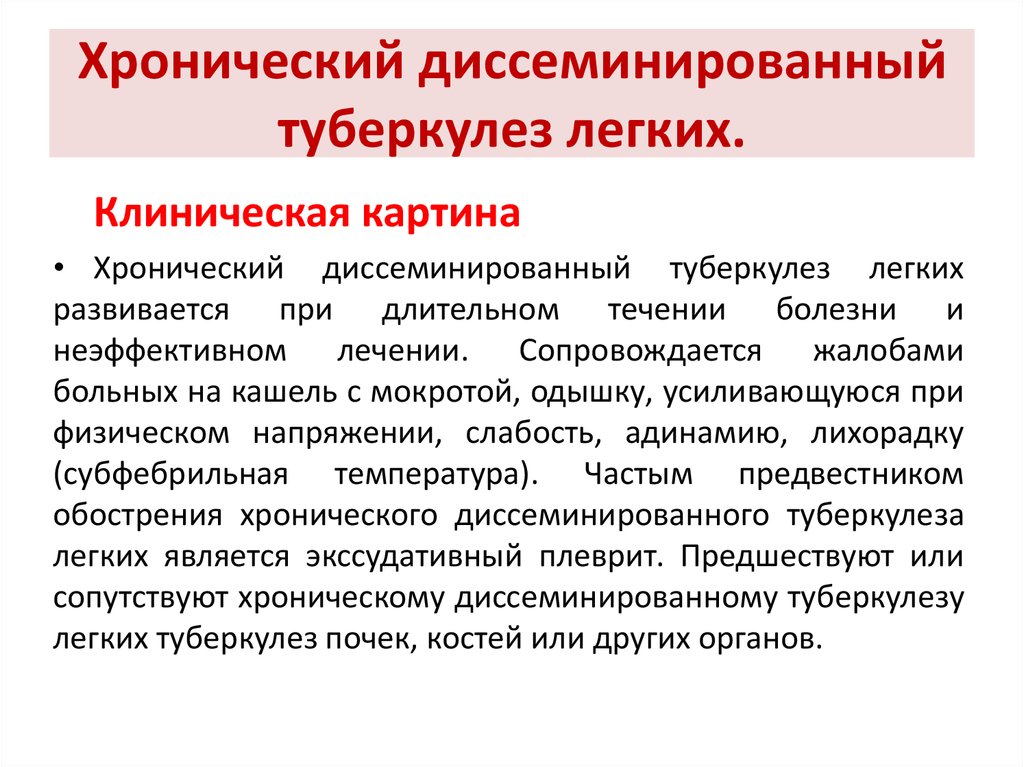

В клинической картине острого гематогенно диссеминированного туберкулеза преобладает